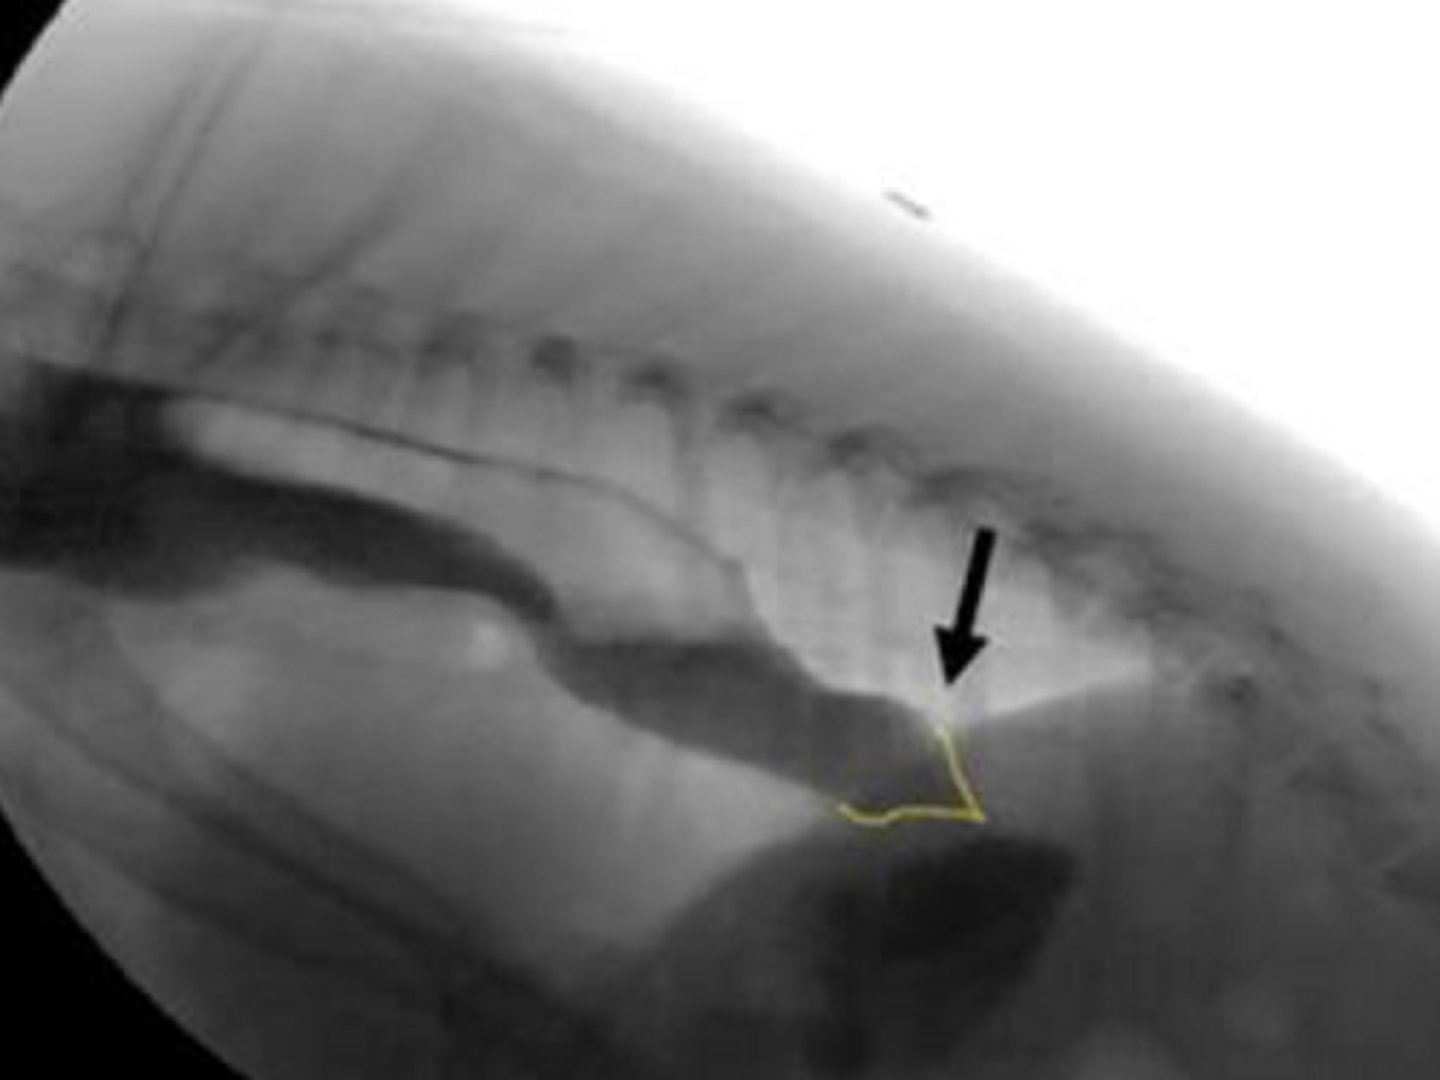

Identify?

LES -AS - bird beak sign